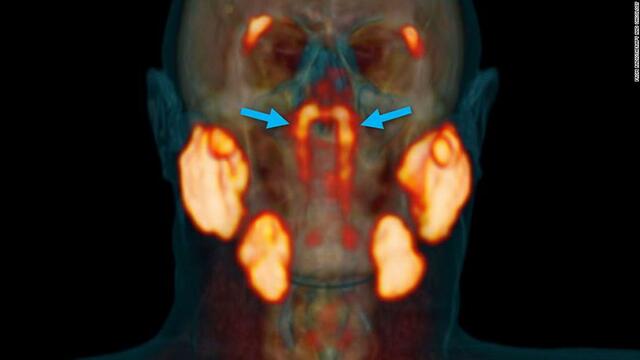

• New glands found

New glands found by doctor Wouter V. Vogel and surgeon Matthijs Valstar at the Netherlands cancer institute.